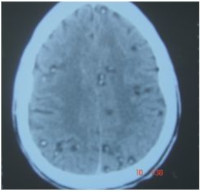

Neurocysticercosis- Temporal Bone Changes on Computed Tomography - A Case Report

Neurocysticercosis is the most common parasitic infection involving the central nervous system and is a major health problem in endemic regions. Bone changes in cysticercosis are rare with paucity of reported cases in both humans and animals. The reported changes are usually erosions, infarctions and necrosis, defects/lytic changes, and heterotopic bone formation. In this report, we present computed tomographic temporal bone changes characterized by thickening with increased density of both the inner and outer tables, a cystic lesion interposed between the thickened calvarium and a defect in the outer table of the right squamous temporal bone. Lesions were also seen in the brain parenchyma, subarachnoid space, and muscles with subcutaneous nodules. Radiologists in endemic areas should add this feature to their gamut of localized thickened cranial vault. This rare and important finding will help us understand the devastating multisystem effects of parasites.